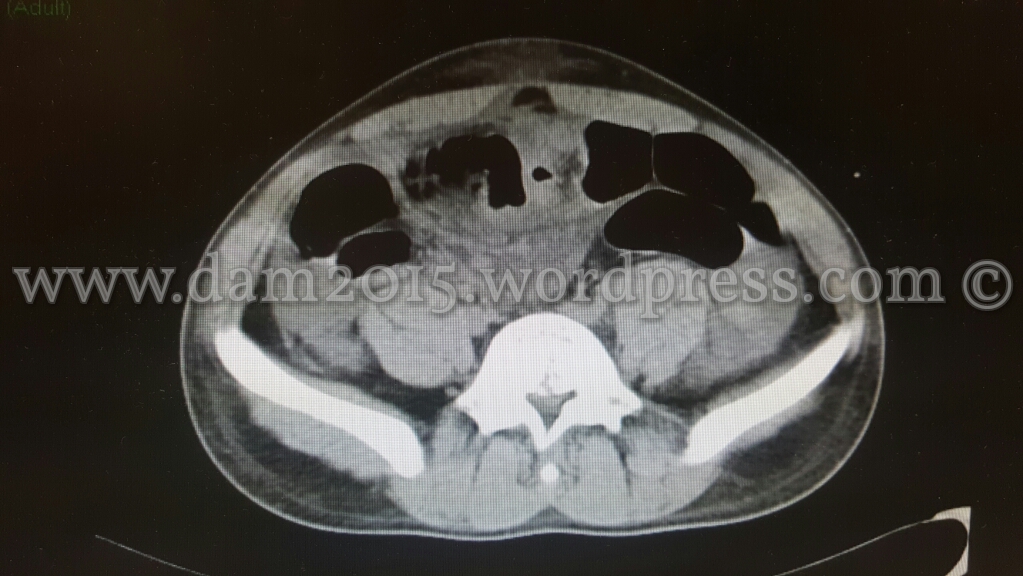

Paziente uomo, 20 anni, caduta accidentale con la bicicletta.

Trauma contusivo diretto dell’impugnatura del manubrio in regione mesogastrica.

Eseguita TC addome che mostrava imbibizione emorragica del tessuto adiposo sottocutaneo della parete addominale in sede mesogastrica e del tessuto adiposo omentale contiguo, peraltro lievemente erniato attraverso la cicatrice ombelicale.